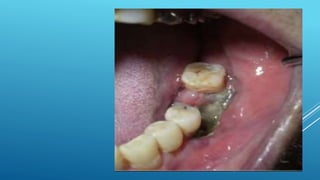

CHRONIC OSTEOMYELITIS WITH PROLIFERATIVE

PERIOSTITIS (GARRE’S OSTEOMYELITIS)

Focal gross thickening of the periosteum with

peripheral reactive bone formation resulting from mild

irritation or infection

Common in children and young adults especially in

mandible

Most common cause is dental caries with periapical

infection or overlying soft tissue infection

GARRE’S OSTEOMYELITIS

Toothache or pain in the jaw and

bony hard swelling on outer surface

of the jaw

Most characteristic finding is on the

radiograph